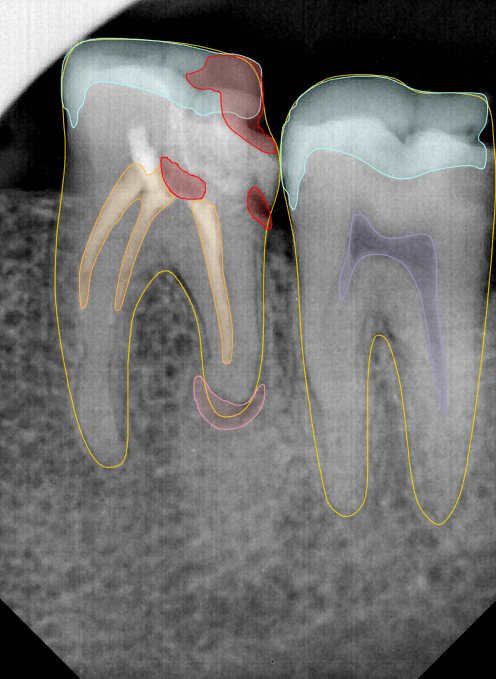

CR/DR 牙齿分割阶段记录

当前进展

- 完成了 CR/DR 牙齿相关分割训练

- 当前结果已经达到阶段预期,但仍有细节问题需要继续处理

相关测试

遇到的问题

- 训练过程中出现过 mask 下移问题

- 部分结果会出现 box 填充异常

- mask 边缘仍然有比较明显的锯齿感

参考

第二版算法问题测试

Updated: 2026-04-13(更新日期)

| 第一版 | 第二版 | 是否解决 | |

|---|---|---|---|

![]() | ![]() ![]() 边角识别有问题 龋齿识别不全 牙髓识别不全 | ![]() | 解决 |

![]() | ![]() 边角识别有问题 识别信息有误 自查(牙冠识别不全) | ![]() | 解决 |

![]() | ![]() ![]() 边角识别有误 大范围填充识别遗漏 | ![]() | 解决 |

![]() | ![]() 识别信息不全 | ![]() | 解决 |

![]() | ![]() ![]() 边角问题 牙胶识别不全 牙冠识别不全 | ![]() | 解决 |

![]() 换图片 | ![]() | ![]() 牙冠部分稍微白了一些就识别成小范围修补,部分判断异常 | 部分解决,修复类略敏感,牙冠部分稍微白了一些就识别成小范围修补,部分判断异常。 |

![]() | ![]() ![]() 牙冠识别不全 牙髓不全 根尖炎龋齿识别有误 | ![]() | 解决 |

![]() | ![]() | ![]() | 解决 |

![]() 换图片 | ![]() | ![]() | 解决 |

![]() | ![]() 牙冠识别有误 | ![]() | 解决 |

![]() 换图片 | ![]() ![]() 边角识别有误 | ![]() 修复类敏感 | 部分解决,图像过白,导致修复类判断异常。 |

![]() 换图片 | ![]() 牙冠识别不全 | ![]() 修复类敏感 | 部分解决,图像过白,导致修复类判断异常 |

结论:修复类出现了不鲁棒的情况,后续需要加入轮廓的扩充数据进行增强。